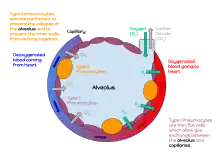

A pulmonary alveolus (pl.: alveoli, from Latin alveolus, "little cavity"), also known as an air sac or air space, is one of millions of hollow, distensible cup-shaped cavities in the lungs where pulmonary gas exchange takes place.[1] Oxygen is exchanged for carbon dioxide at the blood–air barrier between the alveolar air and the pulmonary capillary.[2] Alveoli make up the functional tissue of the mammalian lungs known as the lung parenchyma, which takes up 90 percent of the total lung volume.[3][4]

An alveolus consists of an epithelial layer of simple squamous epithelium (very thin, flattened cells),[13] and an extracellular matrix surrounded by capillaries. The epithelial lining is part of the alveolar membrane, also known as the respiratory membrane, that allows the exchange of gases. The membrane has several layers – a layer of alveolar lining fluid that contains surfactant, the epithelial layer and its basement membrane; a thin interstitial space between the epithelial lining and the capillary membrane; a capillary basement membrane that often fuses with the alveolar basement membrane, and the capillary endothelial membrane. The whole membrane however is only between 0.2 μm at its thinnest part and 0.6 μm at its thickest.[14]

There are three major types of alveolar cell. Two types are pneumocytes or pneumonocytes known as type I and type II cells found in the alveolar wall, and a large phagocytic cell known as an alveolar macrophage that moves about in the lumens of the alveoli, and in the connective tissue between them. Type I cells, also called type I pneumocytes, or type I alveolar cells, are squamous, thin and flat and form the structure of the alveoli. Type II cells, also called type II pneumocytes or type II alveolar cells, release pulmonary surfactant to lower surface tension, and can also differentiate to replace damaged type I cells.[12][15]

Type I cells are the larger of the two cell types; they are thin, flat epithelial lining cells (membranous pneumocytes), that form the structure of the alveoli.[3] They are squamous (giving more surface area to each cell) and have long cytoplasmic extensions that cover more than 95% of the alveolar surface.[12][17]

Type I cells are involved in the process of gas exchange between the alveoli and blood. These cells are extremely thin – sometimes only 25 nm – the electron microscope was needed to prove that all alveoli are lined with epithelium. This thin lining enables a fast diffusion of gas exchange between the air in the alveoli and the blood in the surrounding capillaries.

Type II cells are cuboidal and much smaller than type I cells.[3] They are the most numerous cells in the alveoli, yet do not cover as much surface area as the squamous type I cells.[18] Type II cells (granulous pneumocytes) in the alveolar wall contain secretory organelles known as lamellar bodies or lamellar granules, that fuse with the cell membranes and secrete pulmonary surfactant. This surfactant is a film of fatty substances, a group of phospholipids that reduce alveolar surface tension. The phospholipids are stored in the lamellar bodies. Without this coating, the alveoli would collapse. The surfactant is continuously released by exocytosis. Reinflation of the alveoli following exhalation is made easier by the surfactant, which reduces surface tension in the thin fluid lining of the alveoli. The fluid coating is produced by the body in order to facilitate the transfer of gases between blood and alveolar air, and the type II cells are typically found at the blood–air barrier.[19][20]